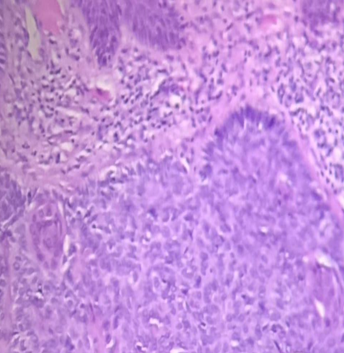

A 58-year-old patient without comorbidities began suffering due to self-detection of a vulvar nodule with pain and bleeding, with menarche at 12 years of age, menopause at 48 years of age, without hormone replacement, and negative cervical screening. Exploration showed a 1cm nodular lesion in the upper third of the right labia majora, rough, regular edges, erythematous, without color changes on acupressure, non-painful, fixed to superficial planes, without adjacent lesions. Radical local excision was performed and the histopathological study reported basal cell carcinoma (Figure 1) (Figure 2). Extension studies without evidence of pelvic or inguinal lymph node activity by tomography. During the 2-year follow-up, she has not presented recurrence.

Figure 2 Microscopic view of the tumor at highest magnification 40x.